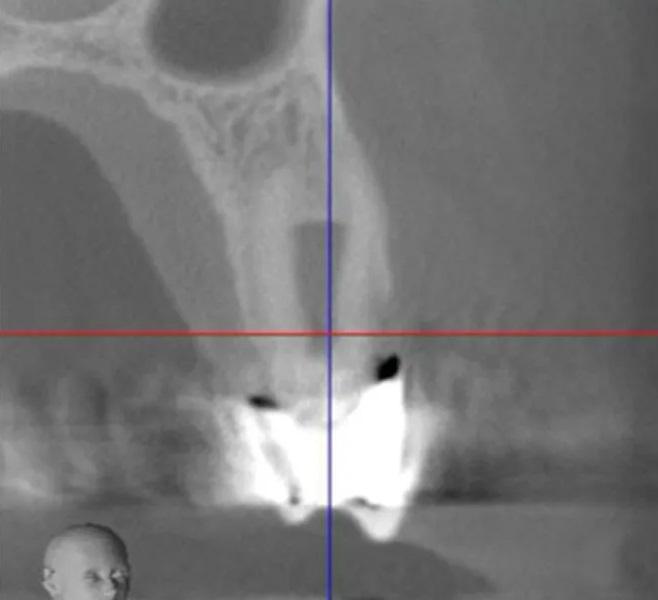

Пациент мужского пола 68 лет был направлен эндодонтистом с диагнозом симптоматический необратимый пульпит с нормальными периапикальными тканями и значительной потерей костной ткани с вовлечением фуркации у первого премоляра верхней челюсти слева (зуб № 2.4). Из-за состояния пародонта была показана реабилитация с помощью имплантационной реставрации. Конусно-лучевая компьютерная томография (КЛКТ) выявила потерю кости с дистальной стороны пораженного зуба, размером 5 мм в ширину и 9 мм в длину соответственно, с вовлечением альвеолярного костного гребня (Фото 1 – Фото 4).

Фото 3. Предоперационный корональный срез КЛКТ первого премоляра верхней челюсти слева.

Фото 4. Предоперационный сагиттальный срез КЛКТ первого премоляра верхней челюсти слева, демонстрирующий область рентгенопрозрачности, вовлекающую более двух третей корня, включая пришеечную область и альвеолярный костный гребень.